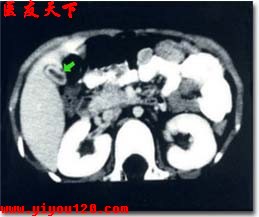

膽囊造影和B型超聲肝膽掃描是診斷慢性膽囊炎很有價值的檢查方法。膽囊造影可以發現膽結石、膽囊縮小變形,以及濃縮和收縮不良等情況,有時膽囊不顯影。B超檢查除了可探查出膽結石和膽囊外型改變以外,還能看到膽囊壁有變毛糙、增厚等徵象。有上述症狀的病人,應及時就醫,通過以上檢查,一般可以明確慢性膽囊炎的診斷。

急性發作時與急性膽囊炎的實驗室檢查相同,無急性發作時可無異常改變。B超檢查可探知膽囊的大小、壁厚薄、有無結石等。口服膽囊造影檢查可觀察膽囊收縮功能是否存在、膽囊內有無結石等。